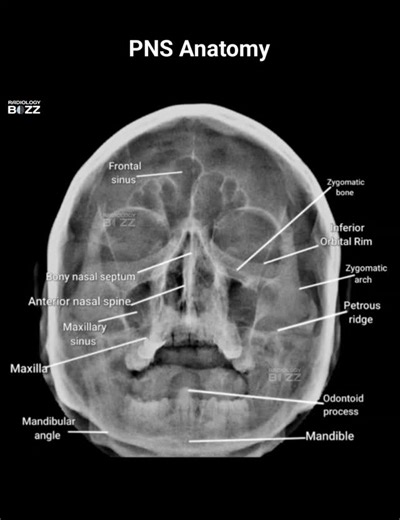

PNS Anatomy

🩻✨ PNS View Anatomy — ✨👃 Here’s a beautifully labeled Paranasal Sinus (PNS) X-ray, showcasing the vital bony and sinus structures of the facial skeleton — a must-know for every radiology professionals! 💀📸 This view helps assess the frontal, maxillary, and ethmoidal sinuses, along with surrounding facial bones for sinusitis, fractures, or other pathologies 🧠 The PNS (Waters) view is obtained with the orbitomeatal line angled 37° to the detector — allowing clear visualization of the maxillary